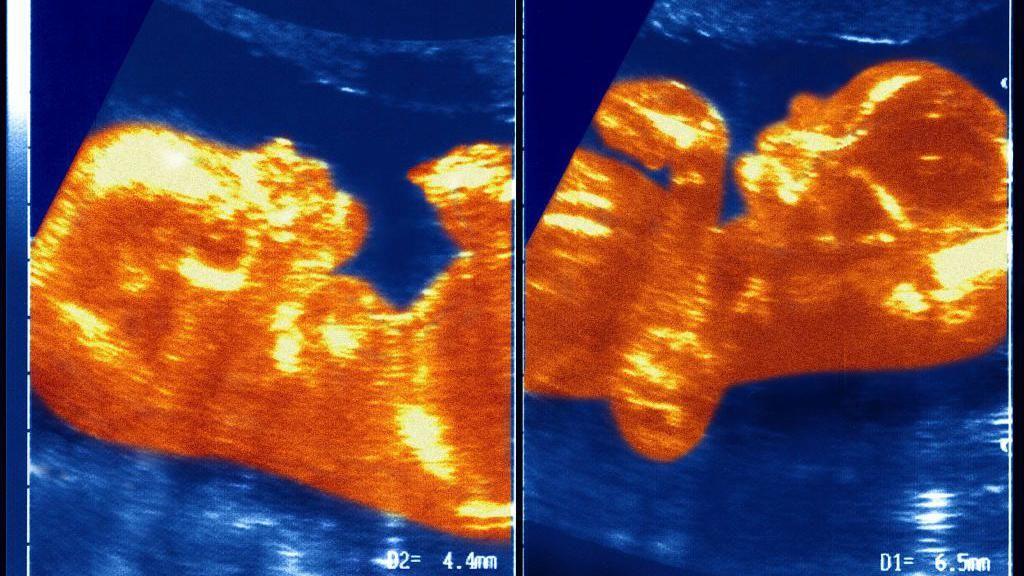

Naučnici pretpostavljaju da su u materici placente Ane Paule i njenog brata blizanca ostvarile neku vrstu kontakta, čime je obrazovana veza između krvnih sudova koji su prenosili krv dečaka u devojčicu.

„Došlo je do transfuzije krvi koju nazivamo sindrom međublizanačke transfuzije.

„U jednom trenutku, vene i arterije blizanaca su se isprepletale u pupčanoj vrpci i on je sav njegov krvni materijal preneo Ane Paule“, objašnjava profesor Masijel.